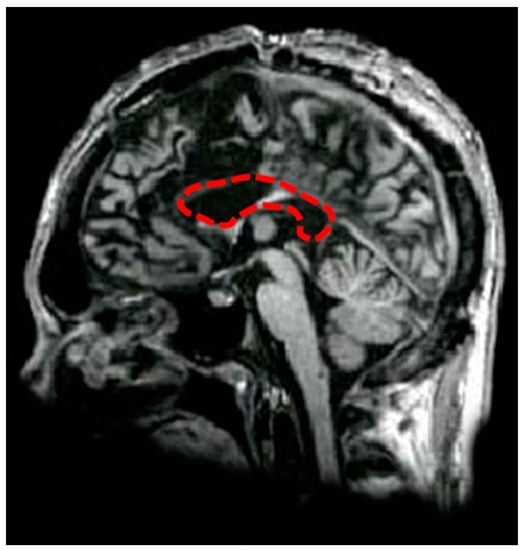

D.D.C. is an Italian male patient suffering from medically intractable epilepsy, who has had the corpus callosum (CC) surgically sectioned in the attempt to avoid the spread of epileptic foci between the cerebral hemispheres. He underwent the first partial section of CC in 1994, when he was 18-year old, and the complete section in 1995; the anterior commissure was also resected (see Figure 1). D.D.C. was 38 years old at the time of the test, his postoperative IQ was 83, and his laterality quotient was +40 (for more details, see [41]). The patient declared that he wrote with his left hand until he was 10, and then he was forced to use the right hand. D.D.C. is free from perceptual or motor impairments, and he has intact linguistic skills in both hemispheres [41]. He was tested at the Epilepsy Center of the Polytechnic University of Marche (Torrette of Ancona), during a pause between routine neurological examinations.

Figure 1. Midsagittal MRI of patients: the figure shows D.D.C.’s brain, showing the complete absence of callosal fibers (in the area delimited by the red-dashed line).